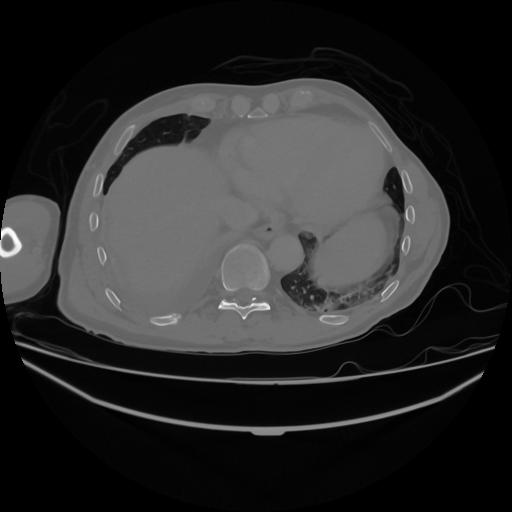

5 CUERPO,CE,Vol,1.0,CUERPO,,